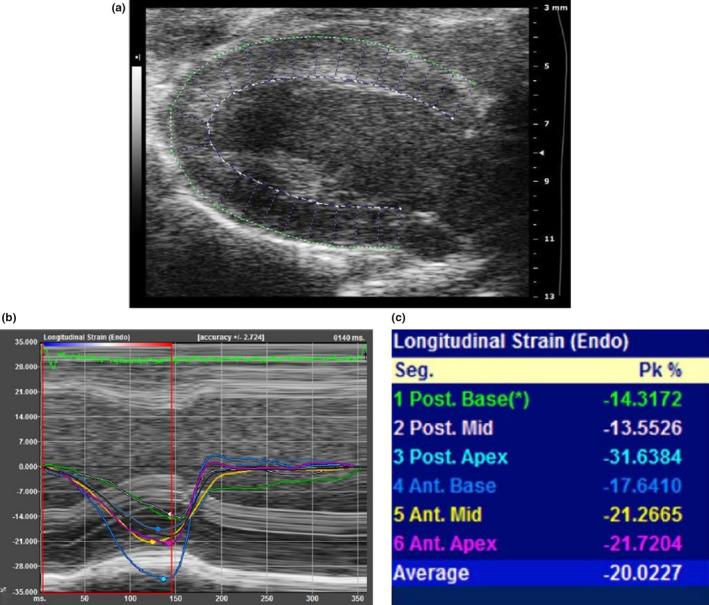

A total of 135 female Syrian hamsters were anesthetized and studied with a small animal dedicated echocardiography system. Echocardiography measurements were obtained from M-mode and B-mode images. Feasibility and 95% reference intervals were obtained for LVEF using three different approaches: LVEF_Teichholz (from M-mode linear measurements), LVEF_BMode (from area-length method), and LVEF_ STE (from strain), and for global longitudinal (GLS), circumferential (GCS), and radial (GRS) endocardial strain. Reproducibility was assessed as intra-class correlation coefficients.

RESULTS

Feasibility of LVEF and endocardial strain was high (95% in FEVE_Teichholz, 93% in the LVEF_BMode, 84% in the LVEF_STE, 84% from PSLAX, and 80% from PSSAX). Values of LVEF_Teichholz were significantly higher than values of LVEF_BMode, and LVEF_STE-derived methods (59.0 ± 5.8, 53.8 ± 4.7, 46.3 ± 5.7, p < 0.0001). The 95% reference intervals for GLS, GCS, and GRS were respectively -13.6(-7.5;-20.4)%, -20.5 ± 3.1%, and + 34,7 ± 7.0%. Intra-class correlation coefficients were 0.49 - 0.91 for LVEF measurements, 0.73 - 0.92 for STE, with better results for LVEF_Teichholz and GLS.